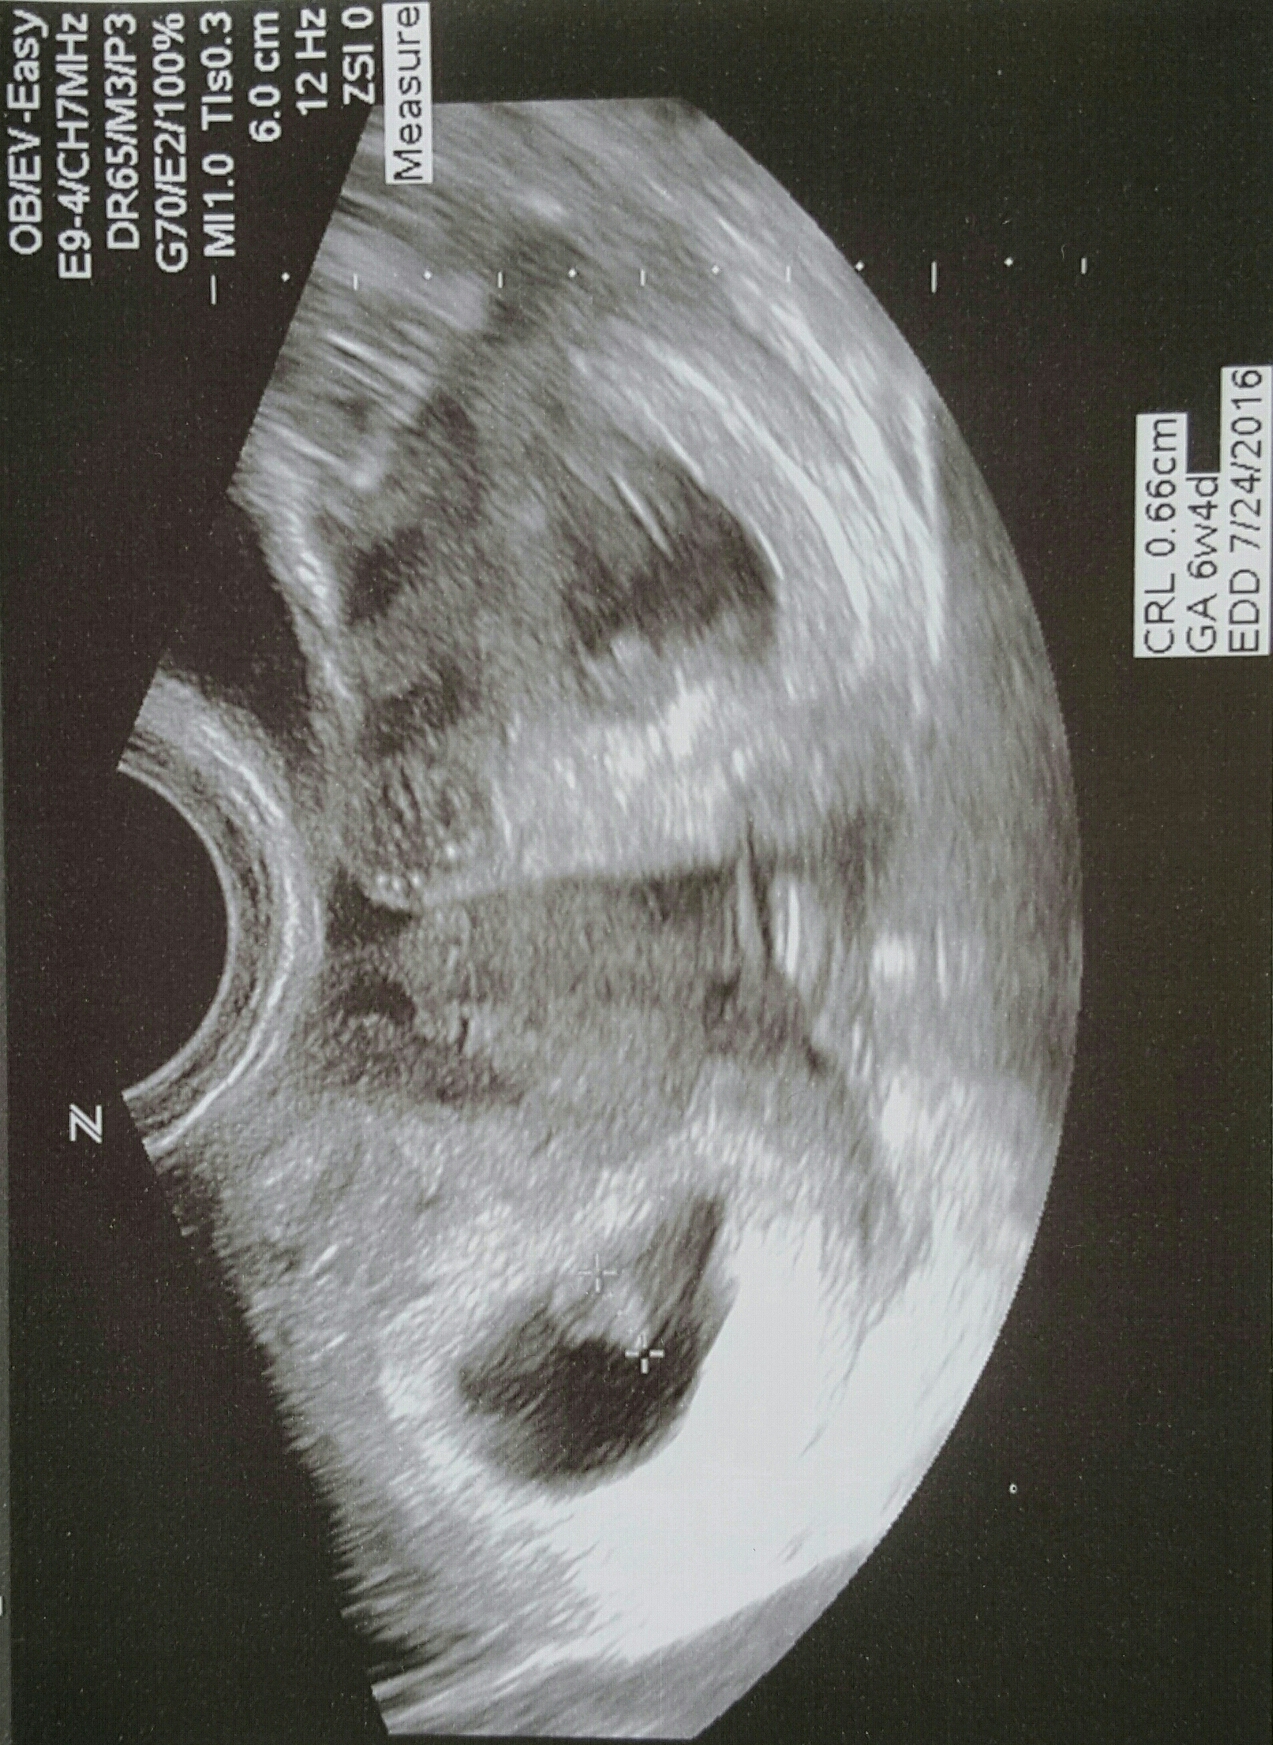

6w4d. Heartbeat at 140. Tech said ultrasound was messing up a bit, which could explain the "mirror twin". Guess we have to wait and see! (Anyone else have this issue?)

Tech said ultrasound was messing up a bit, which could explain the "mirror twin". Guess we have to wait and see! (Anyone else have this issue?)